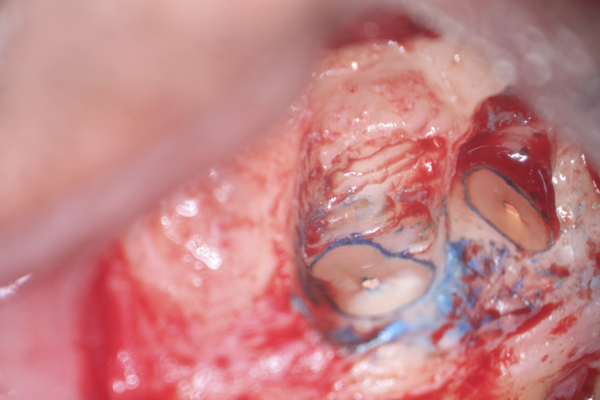

Clinical procedure: In the case of a root-end filling (Figure 15), once the apical 3 mm of the root has been resected (Figure 16) the canal system is then opened and cleaned with surgical ultrasonic tips to create the retro-preparation (Figure 17). After this is completed, the retro-preparation is dried and MTA is then placed and condensed in that space creating the retro-filling (Figure 18 through Figure 20).

Fig 15. Preoperative radiograph.

Figure 15

Fig 16. 3-mm root resection with methylene blue staining.

Figure 16

Fig 17. Retro-preparation with ultrasonic tip.

Figure 17

Fig 18. MTA placed as a retro-filling.

Figure 18

Fig 19. Postoperative radiograph.

Figure 19

Fig 20. 6-month follow-up radiograph.

Figure 20